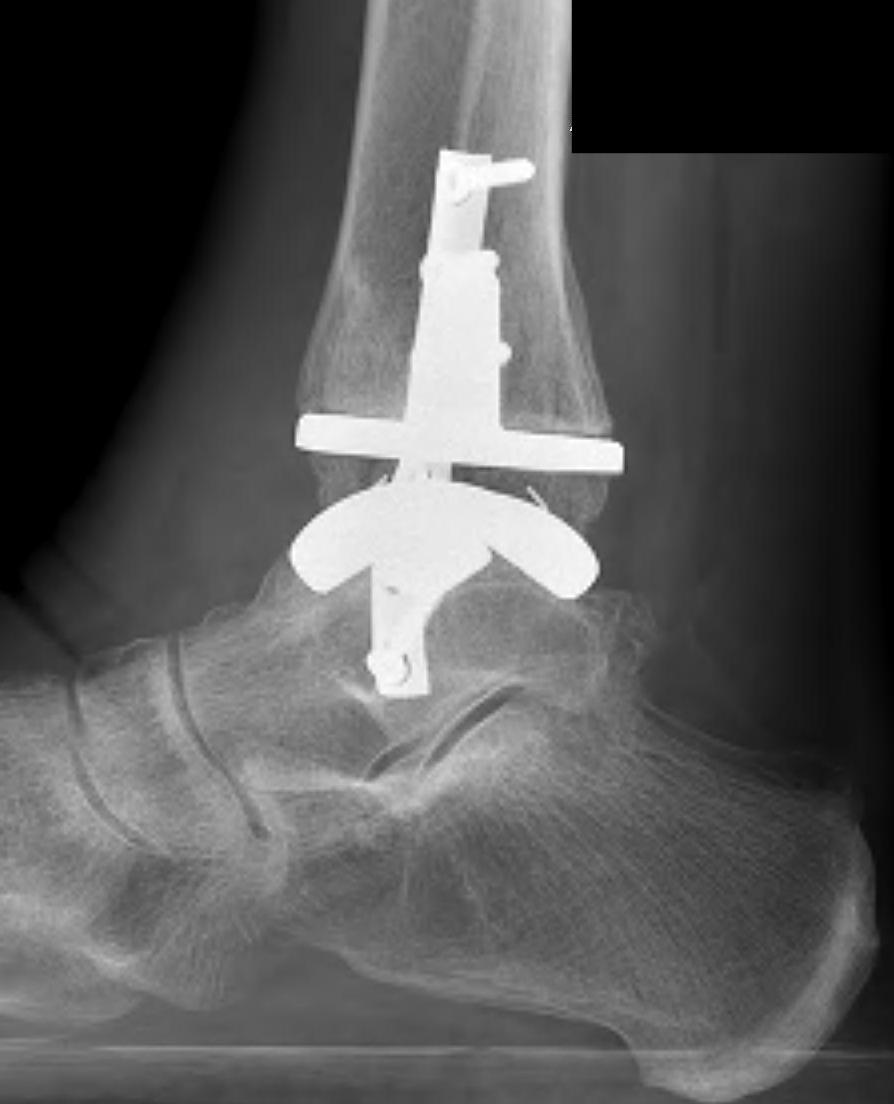

B. Lateral approach and fibular osteotomy

Zimmer Biomet Trabecular Metal PDF

Vumedi fibula osteotomy approach for total ankle arthroplasty

Tibial cut

- distal alignment jig / extramedullar jig +/- image intensifier +/- patient specific jigs

- resect few mm above eroded bone

- preserve medial and lateral malleolus

Talar dome resurfacing

- jig to make chamfer cuts

Insert mobile / fixed bearing